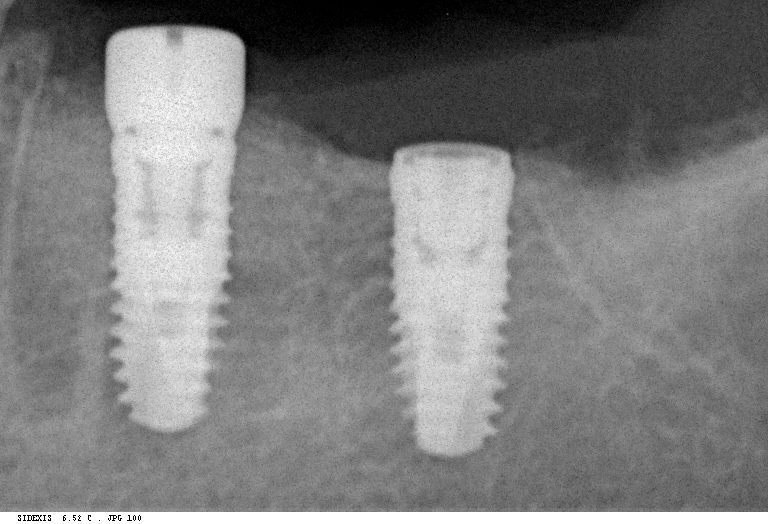

Рентген имплантов Alpha Bio: диагностика и качество